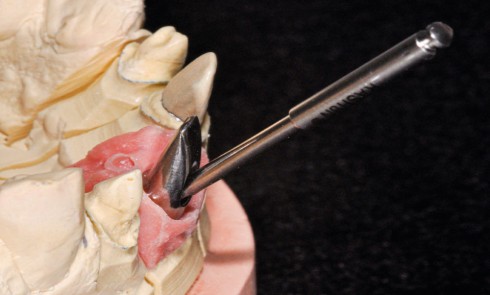

Article réservé à nos abonnés L’implantoplastie pour le traitement des péri-implantites : revue systématique de la littérature. Partie 1

Résumé Objectifs > La péri-implantite, pathologie d’origine bactérienne, affecte 20 % des implants et 10 % des patients. Il n’existe pas de...